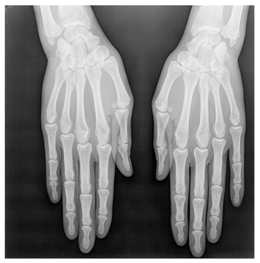

In this section, we present and analyze the results obtained with the proposed method, and compare it to methods proposed in similar works. The proposed watermarking system is implemented using MATLAB and executed on a Windows machine with the following characteristics: Intel R Core i5 processor, 4 GHz, 4 GB RAM, and Microsoft Windows 8 Professional operating system platform. In our experiments, we have used DICOM images of size 512 × 512 pixels as shown in Table 1.

Table 1.

Original images.